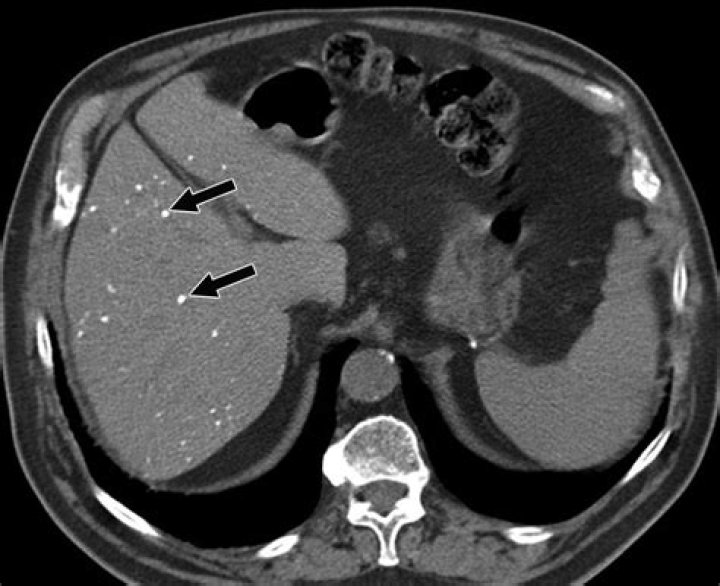

The most common source of calcified hepatic lesions is inflammatory conditions such as granulomatous diseases (e.g., tuberculosis). The calcification typically involves the entire lesion and appears as a dense mass that can produce artifacts on computed tomographic (CT) scans.

The main causes of hepatic calcification are infections-e.g. tuberculosis, histoplasmosis, brucellosis, schistosomiasis, hydatid cyst, cytomegalovirus, toxoplasmosis, Pneumocystis carinii infection, chronic amebic or pyogenic abscess, and chronic granulomatous disease of childhood.

A calcified granuloma is a specific type of tissue inflammation that has become calcified over time. When something is referred to as “calcified,” it means that it contains deposits of the element calcium. Calcium has a tendency to collect in tissue that is healing.